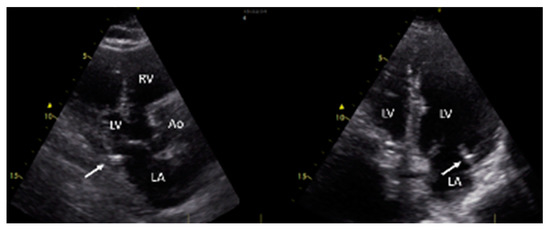

3.2. Evidence of MAC and Clinical Characteristics Based on MAC Status